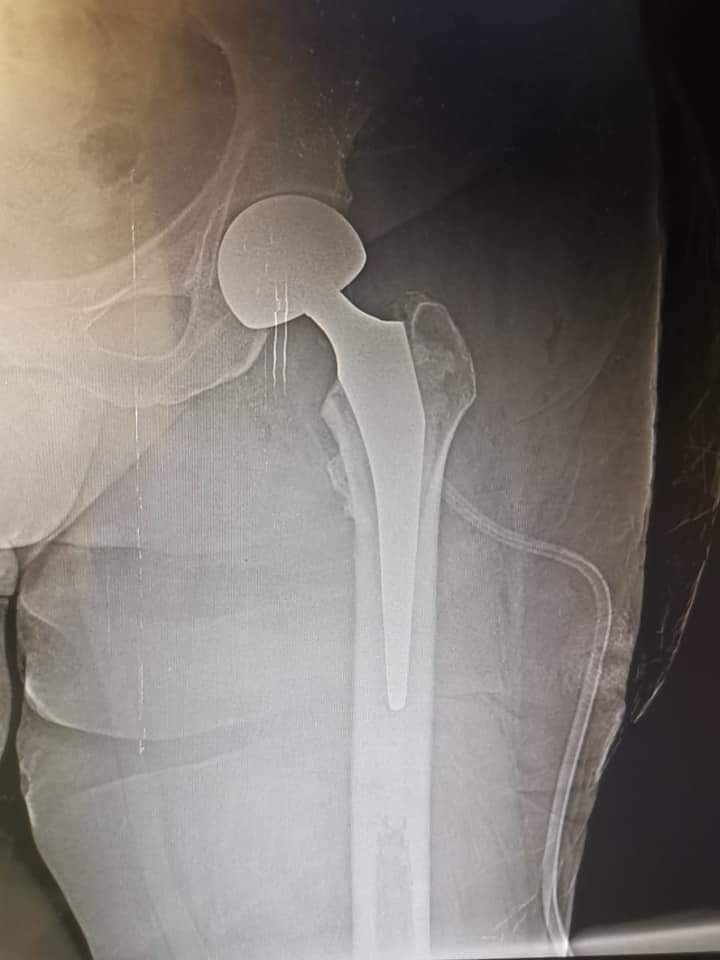

نجح فريق طبي لجراحة العظام بمستشفي أبورديس المركزي بجنوب سيناء في إجراء تركيب وتثبيت مفصل ثنائي القطبين لسيدة تبلغ من العمر ٦٦ عاما.

وتم تحضير الحالة للعمليات وإجراء كافة الفحوصات الطبية من رسومات القلب والتحاليل اللازمة للإطمئنان علي حالة القلب والكلي والكبد للتأكد من عدم وجود مشكلات صحية تمنع من الجراحة اللازمة ، ليتمكن الفريق الطبي من تخدير الحالة وإجراء جراحة تركيب وتثبيت مفصل ثنائي القطبين بنجاح .